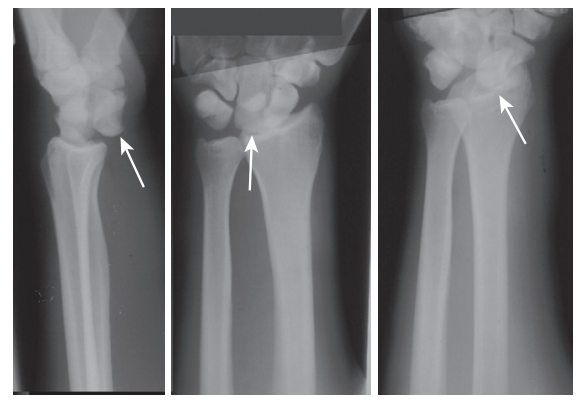

(6.28) A female has pain in her right hand when she fell with force on her outstretched hand. X-rays show an anterior dislocation of a carpal bone. Which bone is dislocated?

A

The lunate is the most commonly dislocated carpal bone because of its shape and relatively weak ligaments anteriorly.